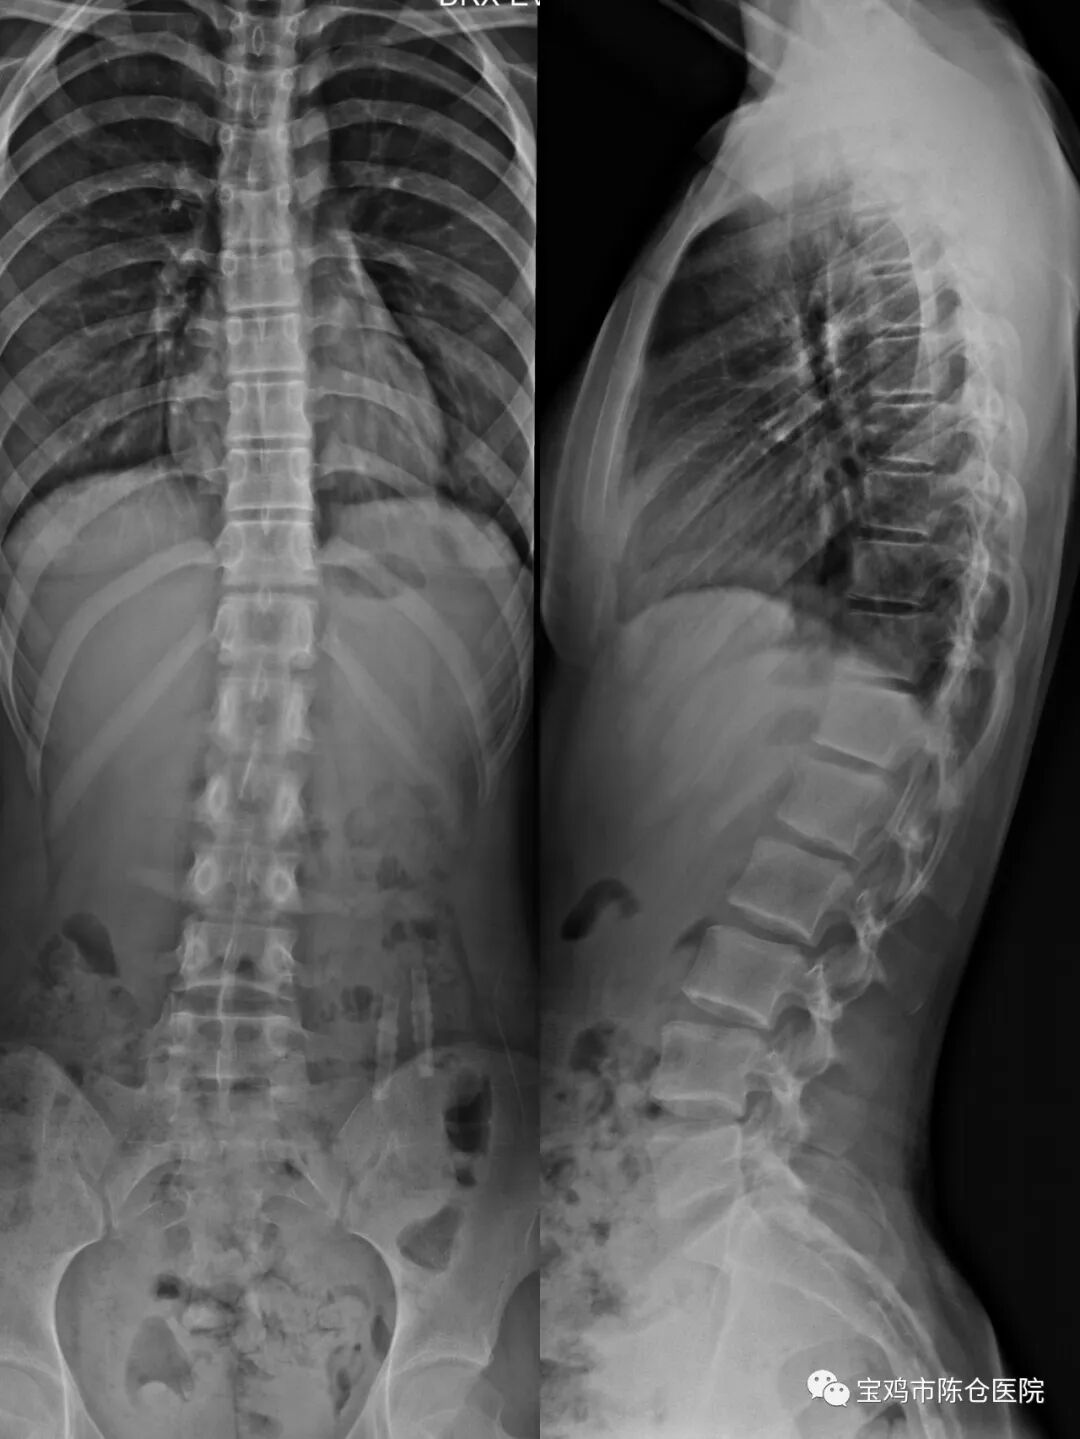

该设备采用大尺寸动态平板探测器,可180度翻转,保证了图像的清晰和超大视野,可满足透视、造影、数字化摄影、数字化点片等多项功能,一次曝光即可完成全结肠、全食道成像,实现了透视定位下同步数字化摄影。

1.大尺寸动态平板探测器:先进的43×43CM大尺寸动态平板探测器,构成的影像链,能够保证图像的高清、动态和大视野。

2.双滤线栅系统:1.8MSID+自动切换的双滤线栅系统,保证了更大的SID大覆盖范围和更好的滤线栅匹配性。

3.影像质量更好:图像数字化采集,采集的所有图像,经数字化处理后图像更加清晰,可以在各种条件下观察细微病变,从而提高诊断准确率。

4.透视剂量明显降低:大大降低辐射剂量。

5.长骨拼接功能:长骨拼接技术具备高速和低剂量的特点,图像采集仅需18-25秒即可完成图像拍摄,同时剂量仅为四次DR拍摄的剂量。

6.多样的临床操作能力:既保证患者在检查过程中的最大舒适感,又让操作变得轻松方便。